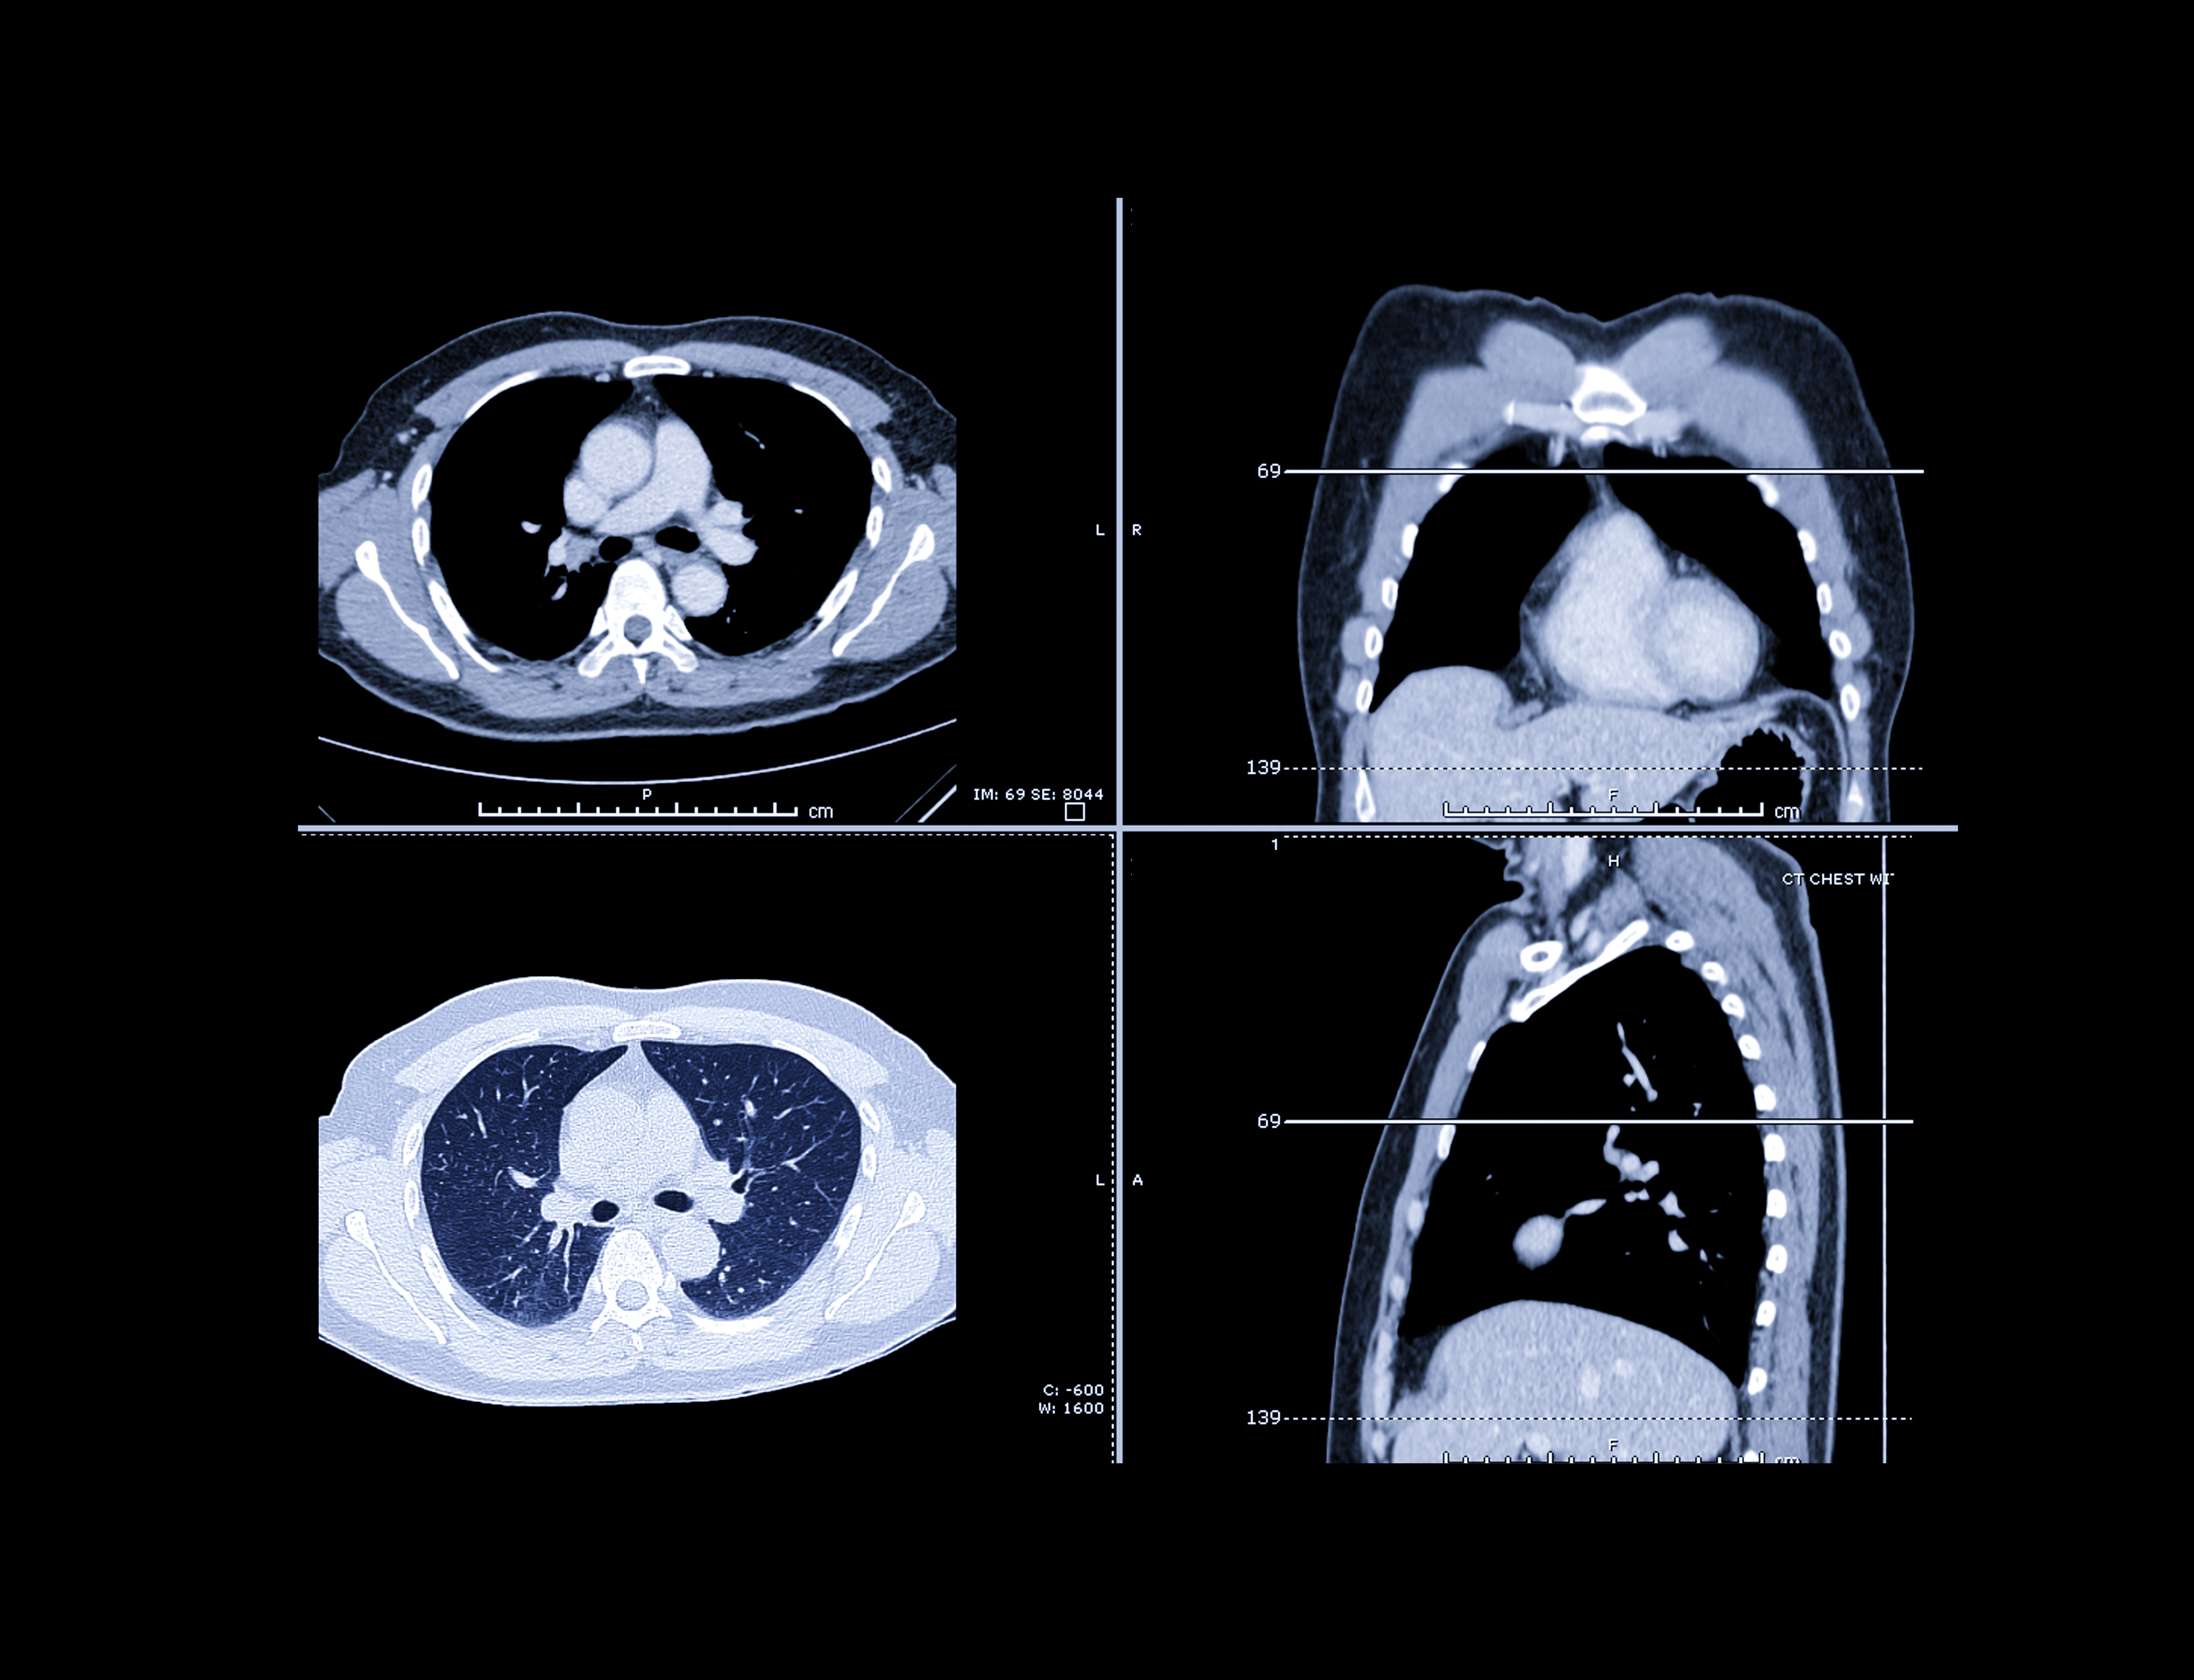

![]() |

| VC protocol at the University of Ulm has evolved over the years with the installation of new MDCT scanners. Since 2001, slice collimation has shrunk from 3.2 mm to 0.9 mm. Chart courtesy of Dr. Andrik Aschoff. |